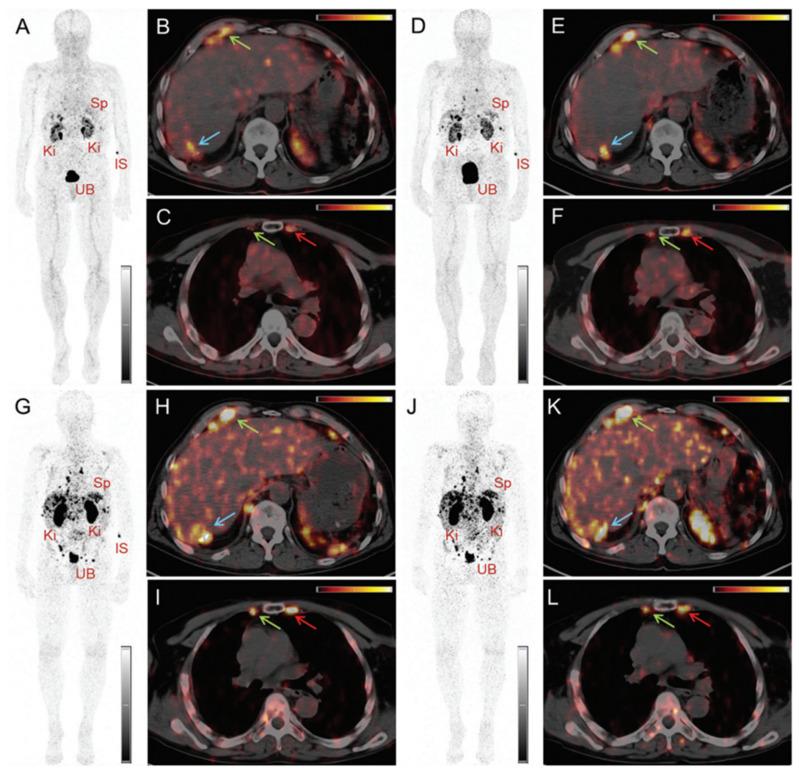

Terbium features four clinically interesting radionuclides for application in nuclear medicine: terbium-149, terbium-152, terbium-155, and terbium-161. Their identical chemical properties enable the synthesis of radiopharmaceuticals with the same pharmacokinetic character, while their distinctive decay characteristics make them valuable for both imaging and therapeutic applications. In particular, terbium-152 and terbium-155 are useful candidates for positron emission tomography (PET) and single photon emission computed tomography (SPECT) imaging, respectively; whereas terbium-149 and terbium-161 find application in α- and β-/Auger electron therapy, respectively. This unique characteristic makes the terbium family ideal for the "matched-pair" principle of theranostics. In this review, the advantages and challenges of terbium-based radiopharmaceuticals are discussed, covering the entire chain from radionuclide production to bedside administration. It elaborates on the fundamental properties of terbium, the production routes of the four interesting radionuclides and gives an overview of the available bifunctional chelators. Finally, we discuss the preclinical and clinical studies as well as the prospects of this promising development in nuclear medicine.